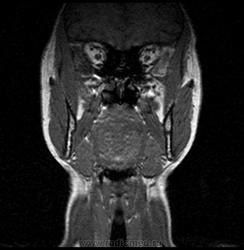

06.06.2011 МРТ - головы и шеи.

Пацентка 36 лет, с жалобами на припухлось в околоушной области справа.

В глубокой доле  правой околоушной железы  на фоне неизмененной паренхимы зона  гетерогенного по Т2, гипоинтенсивного по Т1  с единичными гиперинтенсивными включениями.При контрастировании- накопление контраста диффузное неоднородное и по периферии.Рискну предположить злокачественное образование ( аденокарцинома) с низкой степенью злокачественности( есть капсула, экспансивный рост).Сильно не расстреливайте.

Проблема в том, что перед челюстно-лицевым хирургом стоит распространенность любого объемного процесса, в данном случае все упирается в возмможную травму лицевого нерва и конечно же с дальнейшим его парезом, а ведь женщина  еще молодая. Образование имеет тонкостенную оболочку, по структуре неоднородно, с наличием кальцината, при этом МР-сигнал от окружающих анатомических структур(как костных так и мышечных) не изменен, т.е. об инфильтративном росте речи не идет, в какой то степени доброкачественное. В конкретном случае лицевой нерв с ретромандибулярной веной просто несколько оттеснен.

По гистологии аденома околоушной слюнной железы, но после удаления пока сохраняется парез лицевой мускулатуры, возможно временный.